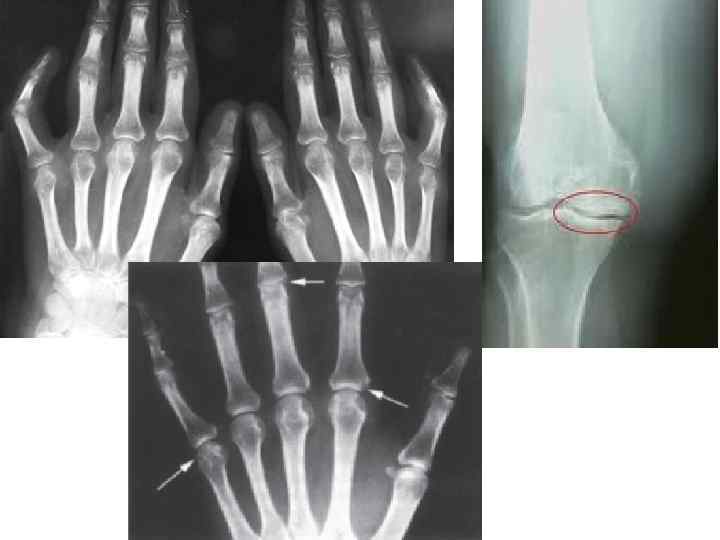

Рентгенологическая стадия • I стадия —эпифизарный остеопороз. • II стадия — эпифизарный остеопороз, разволокнение хряща, сужение суставной щели, единичные эрозии. • III стадия — деструкция хряща и кости, формирование костно-хрящевых эрозий, подвывихи в суставах. • IV стадия —критерии III стадии + фиброзный или костный анкилоз.